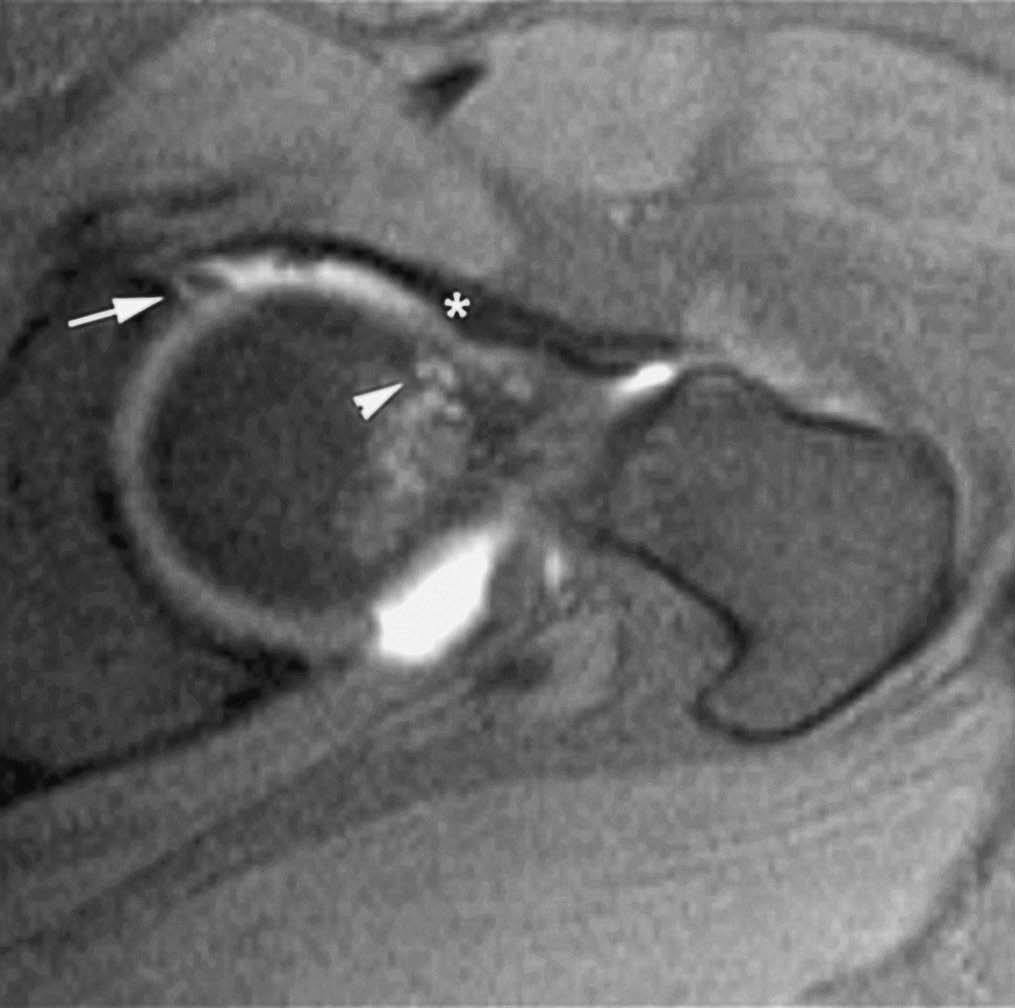

El síndrome de choque fémoro-acetabular está causado por el impacto repetido del cuello femoral sobre el borde del acetábulo debido a una alteración anatómica de la región proximal del fémur --disminución de la anteversión femoral y alteración de la relación normal entre los diámetros de la cabeza y el cuello femoral--. El tratamiento precoz de estas anomalías previene el desarrollo de coxartrosis. La RMA permite visualizar las alteraciones anatómicas del desarrollo, el estado del labrum acetabular, cartílago y cápsula articular (fig. 4)7-9.

Fig. 4.--Síndrome de choque fémoro-acetabular. Corte axial oblicuo de RMA potenciado en T1 con técnica de supresión grasa que muestra una deformidad en la transición cabeza-cuello femoral con edema focal (cabeza de flecha), formación de pequeño quiste sinovial (herniation pit), rotura del labrum antero-superior (flecha) y engrosamiento del ligamento ilio-femoral (asterisco).